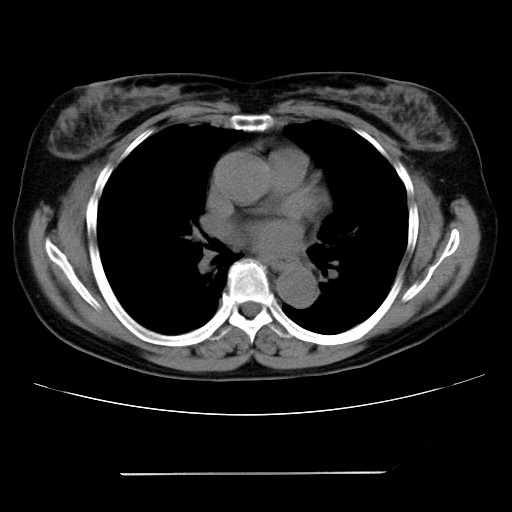

标题: CT24018:女性,62岁,咳嗽4年,无热,胸部CT扫 [打印本页]

女性,62岁,长期咳嗽,既往从事工作有粉尘接触,有高血压病史,110/150mmhg,近日咳嗽加重,脸面浮肿,请大家帮看下,

1、尘肺;2、慢性支气管炎合并肺部感染;3、心影增大(左房、左室大),考虑高血压性心脏病。

能否考虑是尘肺引起的肺源性心脏病?

心包有积液吗?

慢支并肺部炎症;右肺结核球?主肺动脉、右肺动脉影不宽,右心室不大,不支持肺心病;无心包积液。